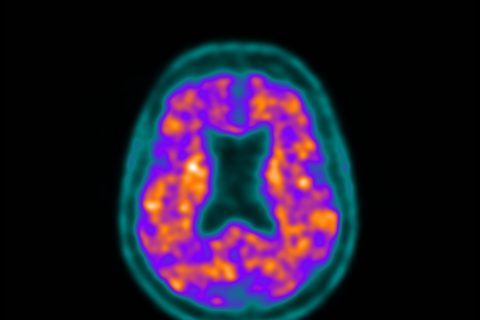

O PSMA11 (68Ga) é um radiofármaco utilizado em estudos de tomografia por emissão de pósitrons (PET) para avaliação de células com metástase de câncer de próstata. O exame é realizado com um antígeno de membrana específico da próstata (PSMA), essa proteína está localizada no tumor da próstata e, como consequência, nos focos de metástases.

Além de diagnosticar esses outros focos da doença, a tecnologia permite aos especialistas avaliarem como está sendo a evolução do tratamento do câncer.